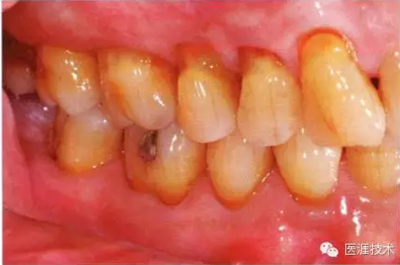

44歲牙周炎女性的臨床照片

44歲患有糖尿病病史(未治愈)。菌斑控制不良。通過牙周探診,全頜有4~8mm的牙周袋,在X光片中可以看到上頜前牙處中度牙槽骨吸收,磨牙處重度牙槽骨吸收。二次齲齒和根面齲齒也有發(fā)生??梢钥吹礁∧[性腫脹,收到刺激后會出血。